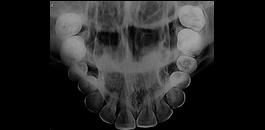

Oclusal

Radiografia utilizada para pesquisa de dentes impactados.